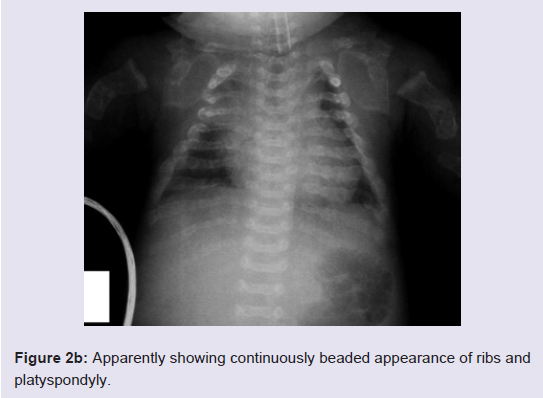

The Turkish female neonate was born at 37th weeks by a cesarean section as the fourth child of a G4-P3-A1 37-year-old healthy mother and non-consanguineous 40-year-old healthy father. Her sibs were clinically normal. Although antenatal follow-up was irregular, fetal ultrasound scan just before birth revealed that femur length was compatible with 19th gestational weeks. Moreover, polyhydramnios was present in prenatal history. Her birth weight was 1900 g (0,4-2 p), length 36 cm (<0,4 p), head circumference 34 cm (75-91 p). APGAR scores wear 1/3 at 1/5 minutes, respectively. She was suffering from jaundice at the postnatal period. On clinical examination 1 day after birth, the head appeared relatively large compared to the body. Furthermore, she had a soft cranium, hypertrichosis on the forehead and arms, low frontal hairline, blepharophimosis, thin lips, micrognathia, low-set, posteriorly rotated ears, narrow and short thorax, severe micromelia with bowing, abnormal groove on the humerus, edema on the dorsum of the hands and feet, and absent palmar creases. Rhizomelic as well as mesomelic shortening of limbs were present. The hips were in flexed and abducted position (Figure 1). She dead two days after birth because of respiratory insufficiency.Routine laboratory blood tests showed leukocytosis, mild anemia, normal calcium, phosphorous and alkaline phosphatase levels, and severely increased LDH values (2880 U/L). Her karyotype was normal.The skeletal overview showed severely reduced but visible mineralization of the calvarium. The thorax was small and bellshaped. The ribs were broad with continuous beading. Mild platyspondyly was detected at the lumbar spine (Figure 2a and 2b). There was significant shortening of the limbs. The long bones of the extremities were broadened, crumpled, deformed and shortened and a fracture line was visible in the right femur. Additionally, the skull was deformed with pressure of the transducer at sonographic examination.

As such, clinical and radiological features of our patient were strongly suggestive of OI type 2, and more specifically OI type 2A. In 1984, Sillence et al. subdivided OI type 2 into three separate subgroups (A, B and C) based on radiological features (Table 1) [12]. In OI type IIA, there is a marked reduction of ossification of the calvarial and facial bones. Long bones are broad and crumpled secondary to repeated fractures. The chest is small, with thickened and shortened ribs that are continuously beaded, indicating multiple fractures. Death invariably occurs, either prenatally or in the postnatal period. In OI type IIB, the skull and long bones are similar to type A, and the degree of deformation of the long bones is less defere, but the ribs are thin and not continuously beaded. Type IIC appeared to be extremely rare and is often not considered anymore. In our patient, the mineralization of the cranium is severely reduced but visible. The ribs were broad and had a continuously beaded appereance. The long bones were short, broad, crumpled and deformed due to callus formation and compression fractures. Considering the radiological signs, the diagnosis OI type 2A was made in our patient.